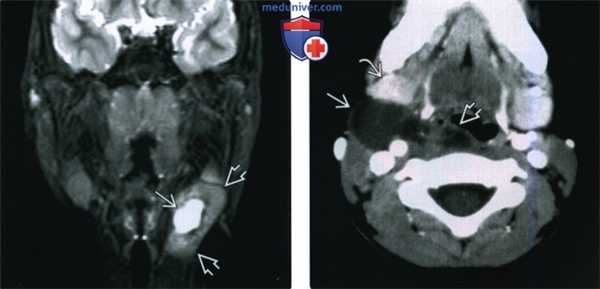

(Слева) При корональной МРТ Т2 ВИ визуализируются остатки тимуса кистозного и солидного характера (такое сочетание является редким) в левой половине шеи.

(Справа) При аксиальной КТ с КУ визуализируется киста тимуса, расположенная в заднем поднижнечелюстном пространстве справа (редкая локализация), смещающая поднижнечелюстную железу кпереди и кнаружи. Киста распространяется также в заглоточное пространство.